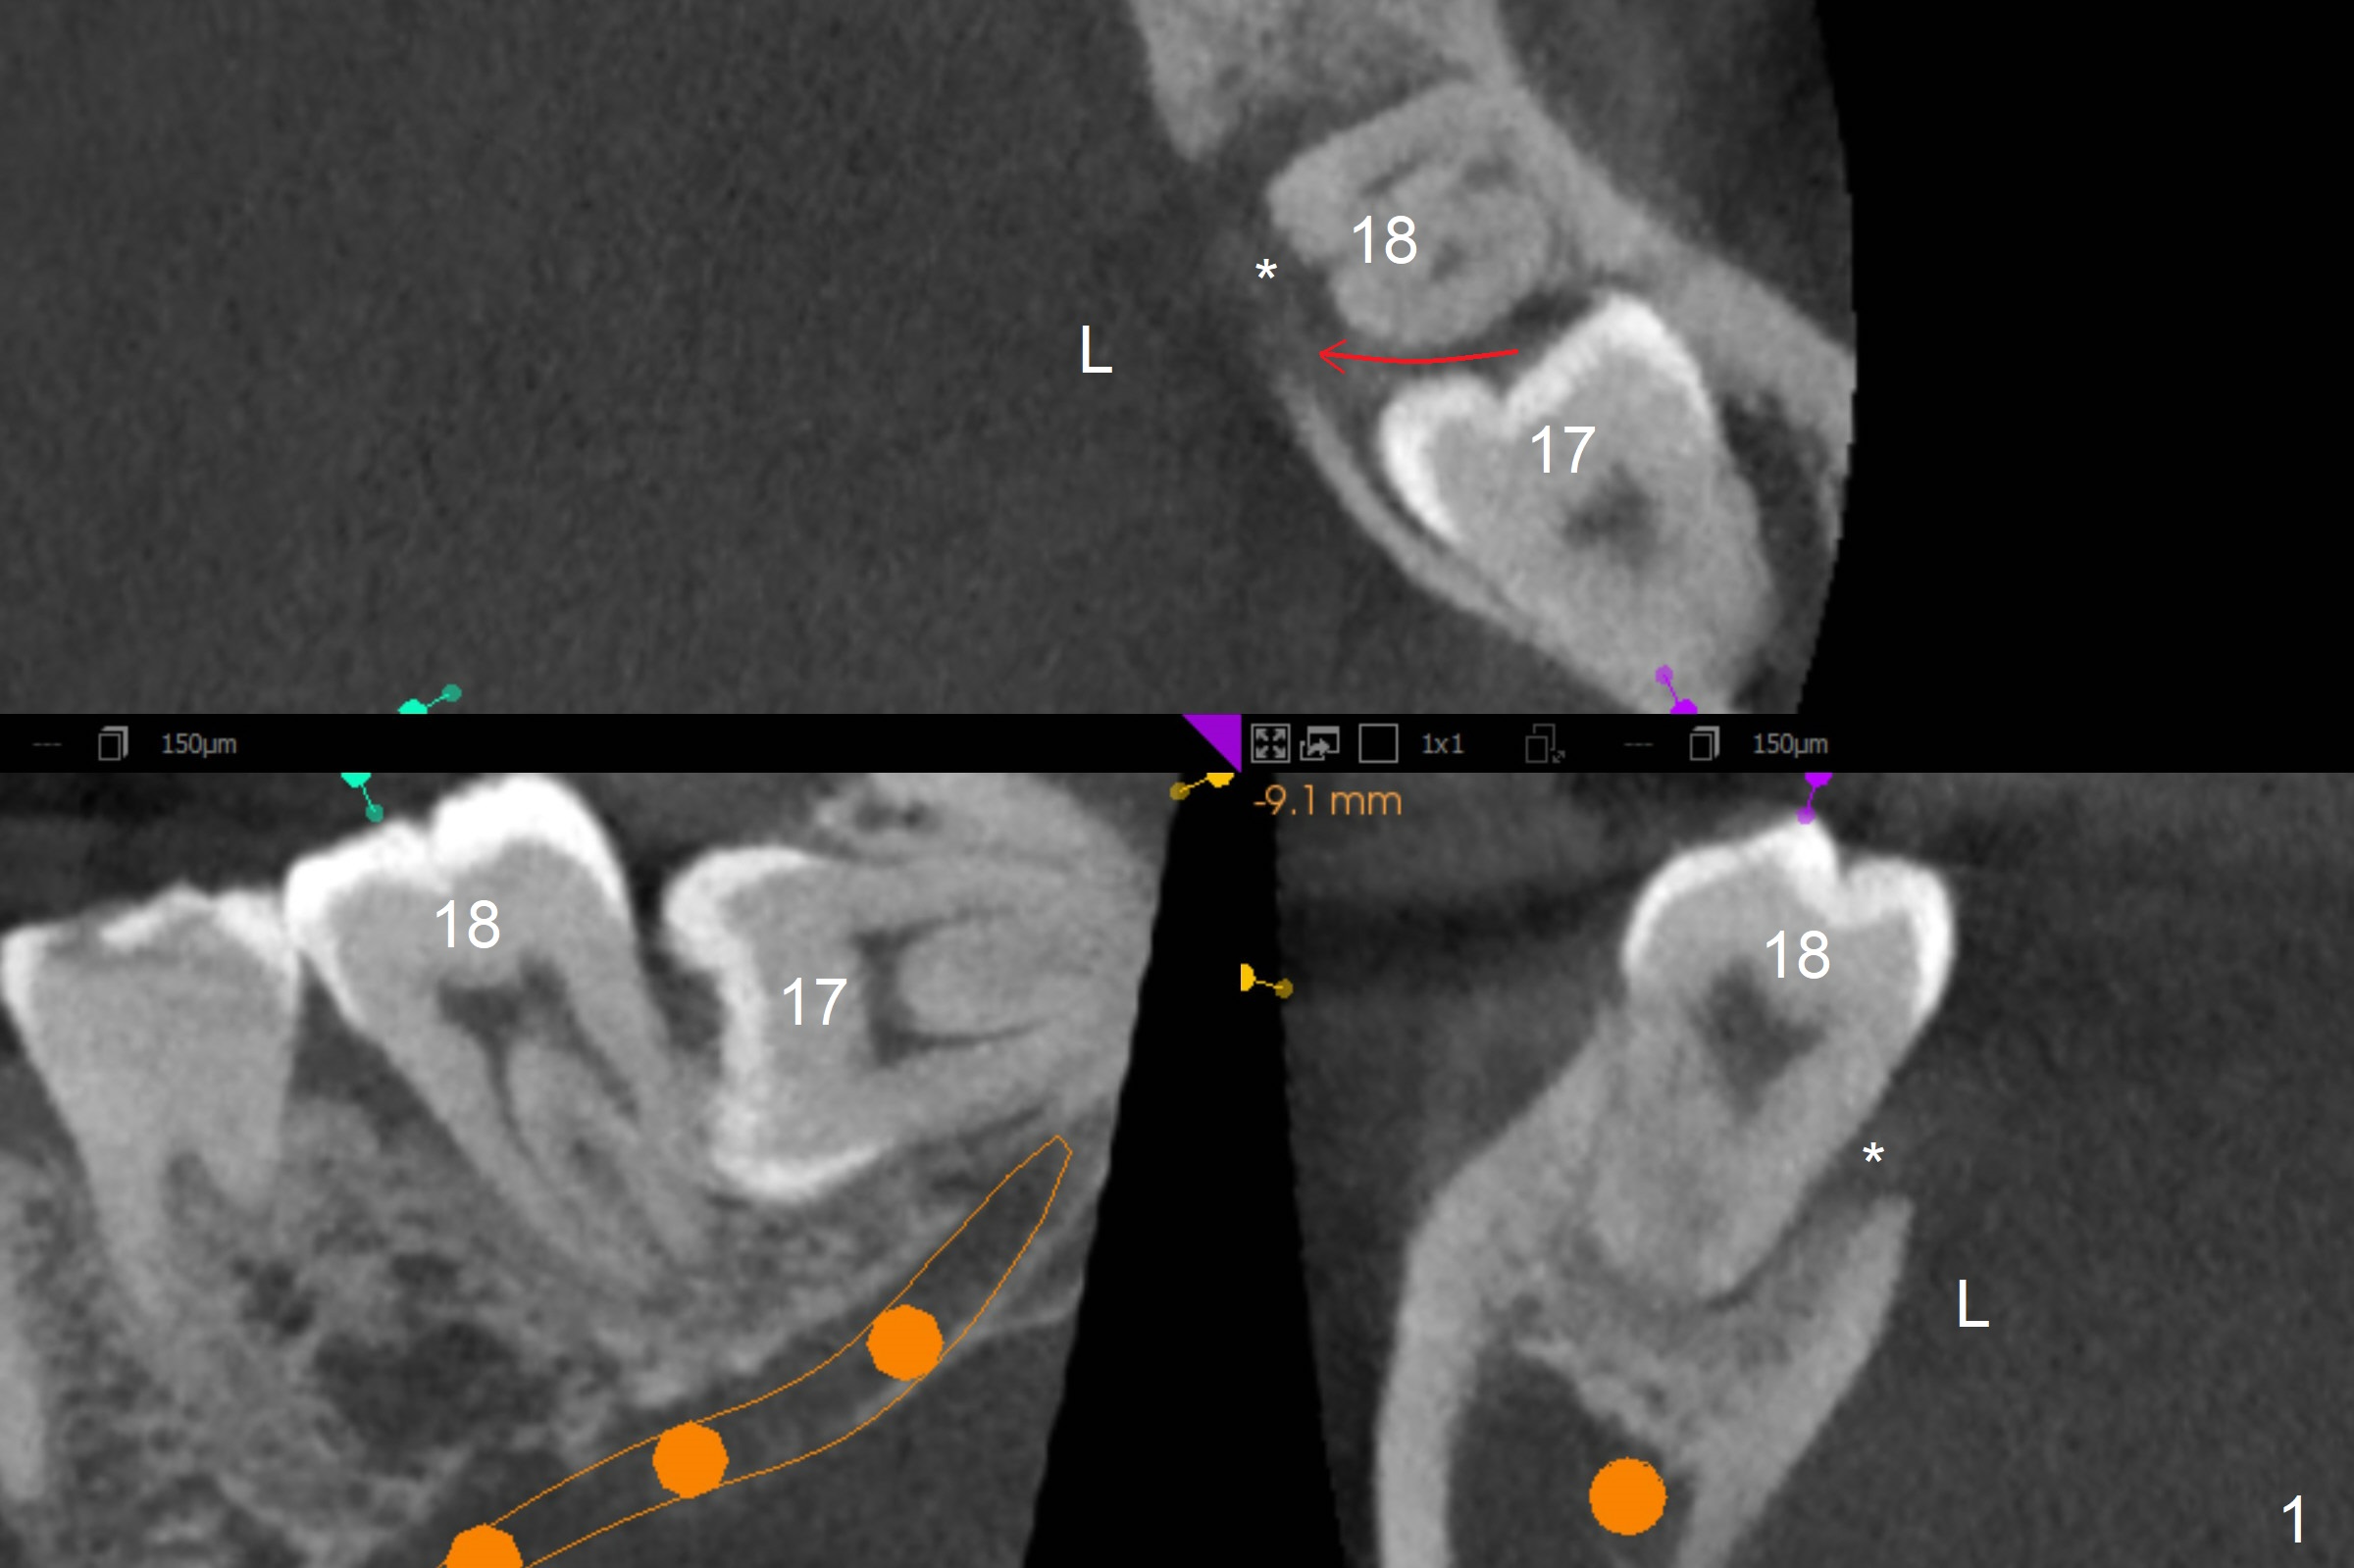

A 40-year-old man removes food debris from the lower left area, probably between #17 and 18, using Water Pik. Initially it looks as if the bone loss lingual (Fig.1 (CBCT with 3 sections) L) to #18 is derived from #17 (red curved arrow). Closer look shows generalized thickened periodontal ligament space at #18 (Fig.2 arrowheads). The patient requests extraction of the tooth #17; the tooth #18 seems non-salvageable. When an immediate implant is placed in the middle of the socket (Fig.3,4 (coronal section)), there is limited amount of the native bone to stabilize the implant (~1 mm). In contrast, there is approximately 5 mm of the native bone for primary stability if the implant is placed in the mesial slope of the fused socket (Fig.5 yellow dashed line). The implant should be placed buccally (B) to reduce the chance of nerve injury (Fig.4,6).